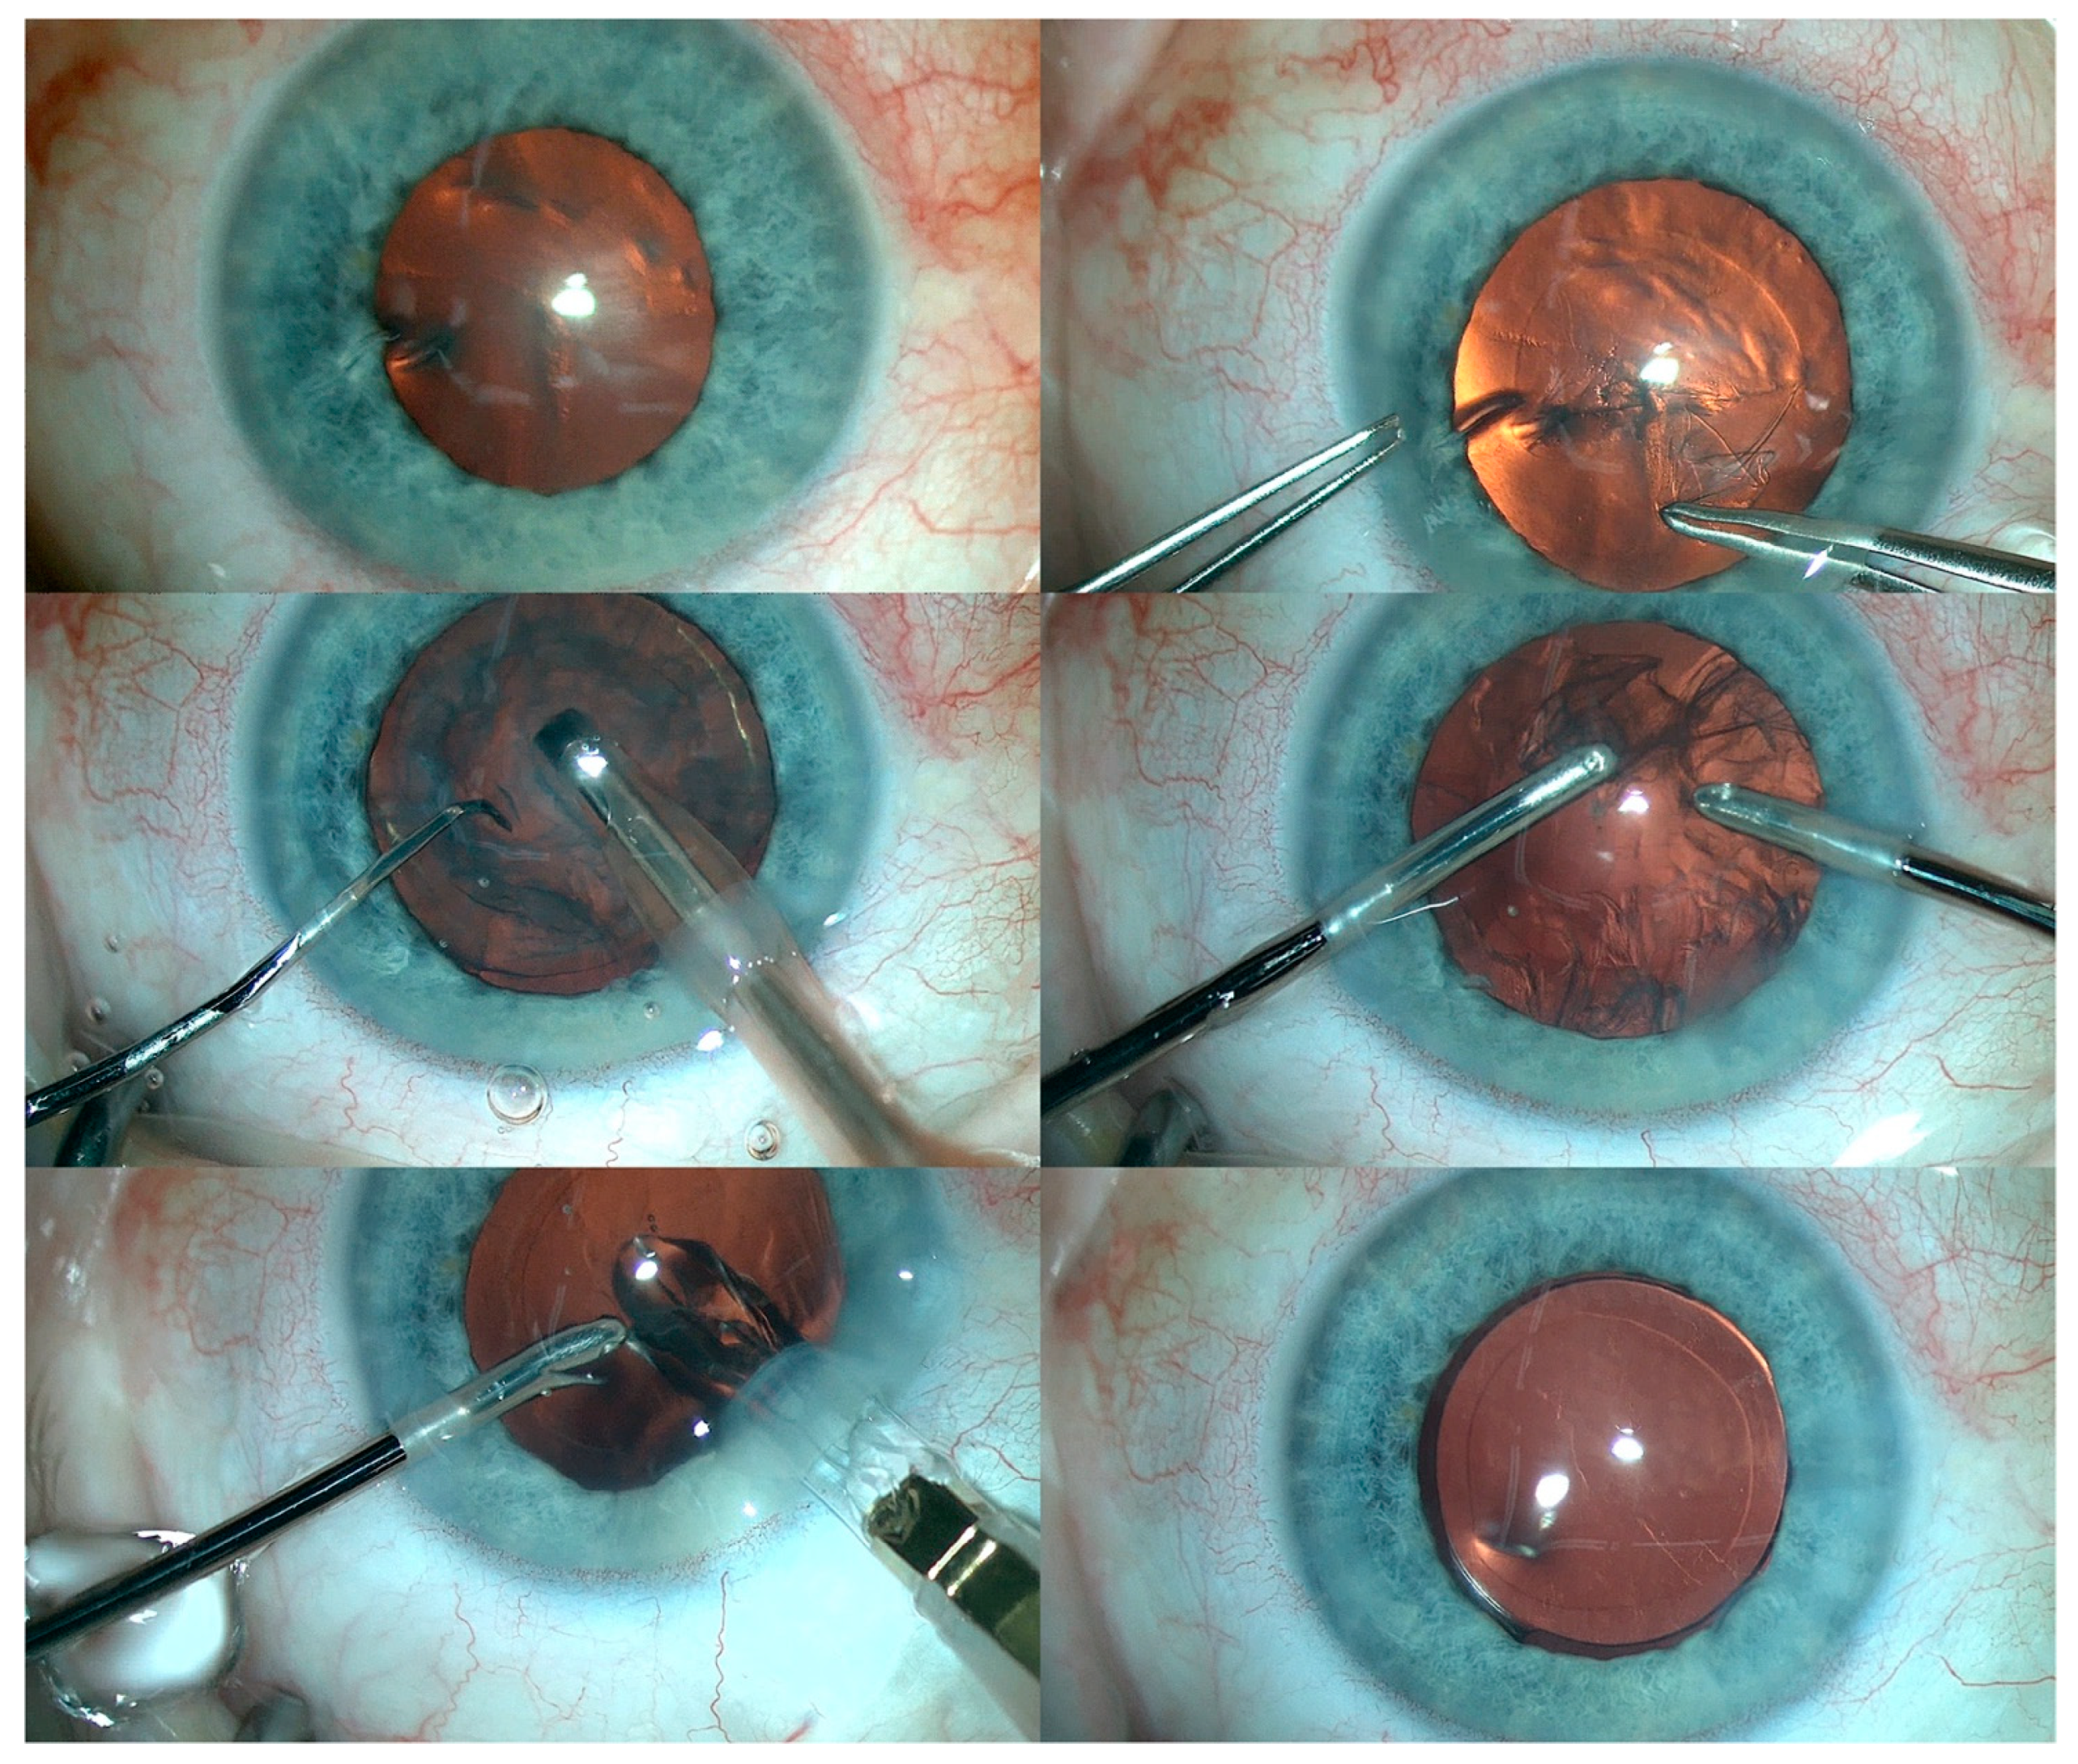

2. Case Report